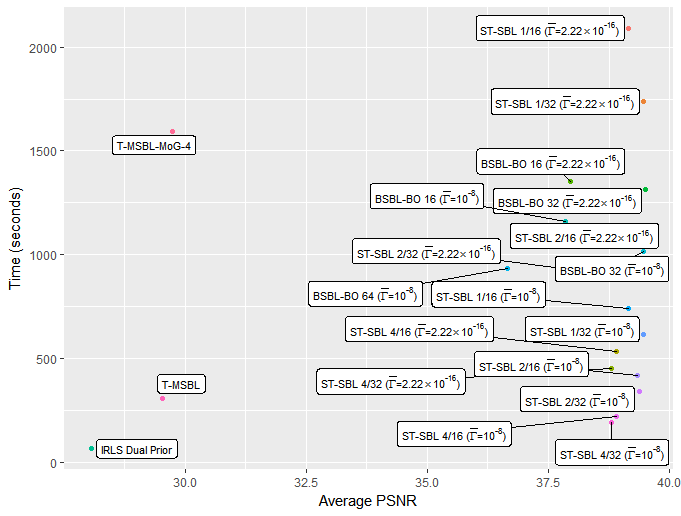

Whilst we are primarily concerned with the quality of the reconstruction, the time taken for various reconstruction methods is of some practical interest. Figures 5 and 6 show plots of average time against the average PSNR achieved. For these timings, the algorithms were run using MATLAB 2014a on computer equipped with an i7-3770 processor and 8GB of RAM. Although processing more than a single column at a time with ST-SBL does not typically lead to improved recovery performance, the drop in performance is minimal, and as seen in figures 5 and 6, there is a significant reduction in computational time required by processing multiple columns at once.

Overall, the best recovery performance was achieved with ST-SBL 1/32 () . However, once we take the computational time into account, we would consider ST-SBL 4/32 () to be the best practical choice, as it offers only a minimal decrease in performance, and a very significant reduction in the computational time required.